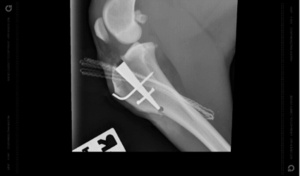

TPLO is widely regarded as the gold standard for cruciate ligament repair, offering excellent long-term outcomes, especially for active and larger dogs. This procedure involves making a curved cut in the tibia (shin bone), rotating it, and securing it in a new position using a specialised plate and screws. By changing the angle of the joint surface, TPLO neutralises the forces that cause instability in a cruciate-deficient knee.

The MMP procedure is considered less invasive than the TPLO, recovery can be quicker, and the surgery can be performed at significantly lower cost but still with excellent outcomes. It involves altering the tibial angle by making a cut in the bone of the tibia and using a special titanium Orthofoam™ wedge implant to advance a portion of the bone (the tibial tuberosity) forwards. This is then fixed in place with a pin & titanium staple. The advancement of the bone causes an increase in tension on the patella tendon, altering the knee’s biomechanics, so the patella tendon takes over the function of the damaged cruciate ligament.